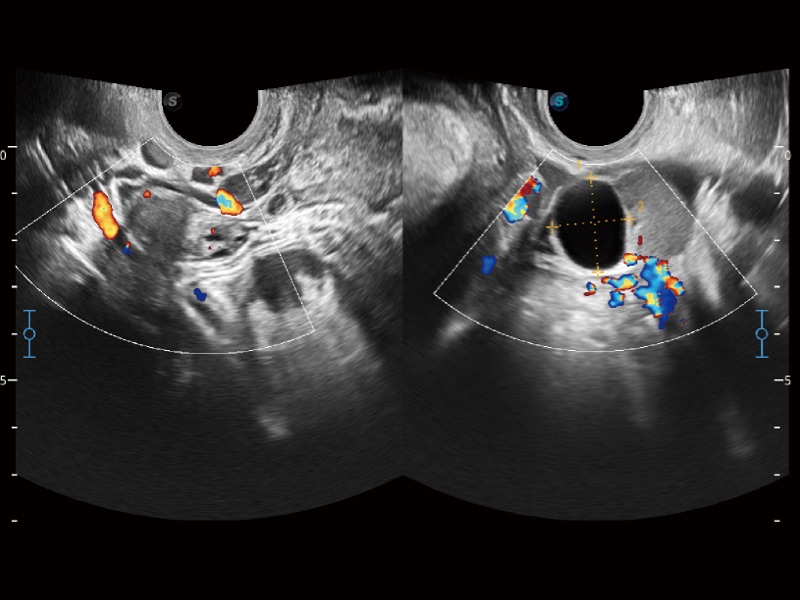

婦產(chǎn)科應(yīng)用

微米成像技術(shù)大大提高了器官和病變的可見(jiàn)性。高清對(duì)比度分辨率將抑制斑點(diǎn)噪聲,同時(shí)保持真實(shí)的組織結(jié)構(gòu)。